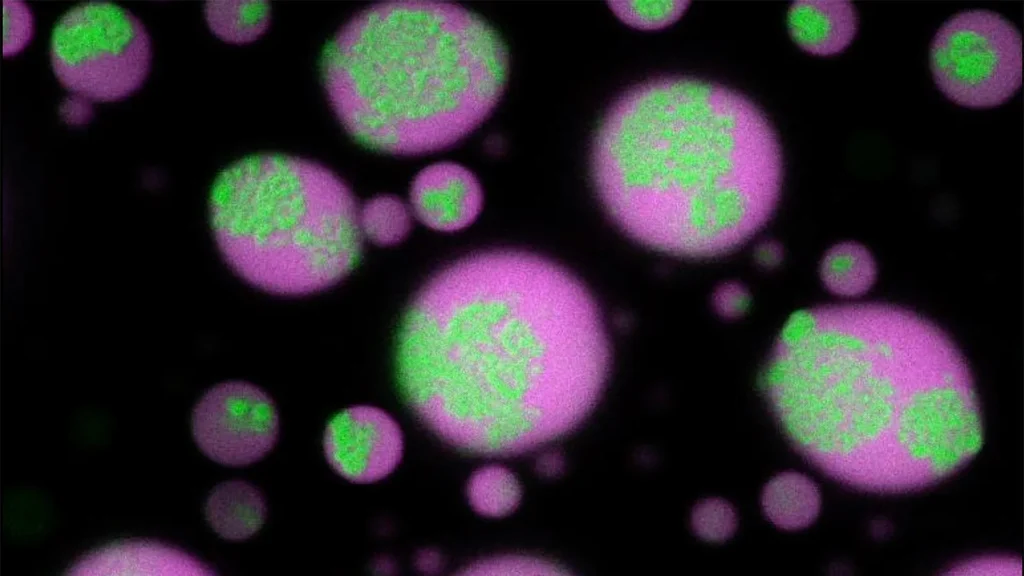

“It’s fascinating to watch these clusters form over time inside dense, droplet-like mixtures of protein and RNA under the microscope. Just as striking, the clusters dissolve when antisense oligonucleotides pull the RNA aggregates apart,” says the study’s corresponding author, Priya Banerjee, PhD, associate professor in the Department of Physics, within the UB College of Arts and Sciences. “What’s exciting about this discovery is that we not only figured out how these clusters form but also found a way to break them apart.”

The condensates are essentially used as hosts by repeat RNAs, disease-linked RNA molecules with abnormally long strands of repeated sequences. At an early timepoint, the repeat RNAs remain fully mixed inside these condensates, but as the condensates age, the RNA molecules start clumping together, creating an RNA-rich solid core surrounded by an RNA-depleted fluid shell.